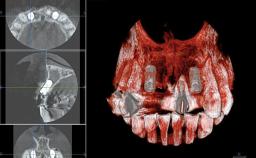

A 45-year-old woman was referred for management of an infection associated with two implant-supported crowns replacing the maxillary central incisors. Two tissue-level implants had been placed and restored with cemented single metal-ceramic crowns in those sites 4 years previously. The patient presented with a draining sinus (i.e. a pathological duct from an abscess cavity to a surface) 3 mm from the midfacial peri-implant mucosal margin of the maxillary right implant crown. She was in good general health, did not smoke, showed a good oral hygiene status, and had no history of periodontal disease. The implants were well positioned. While the patient was very satisfied with the appearance of her crowns, she had noted that the peri-implant soft tissue had receded since their insertion and was concerned about the possibility of further recession.

| Bone Volume | Horizontally and vertically sufficient |

| Anatomic Risk | Low |